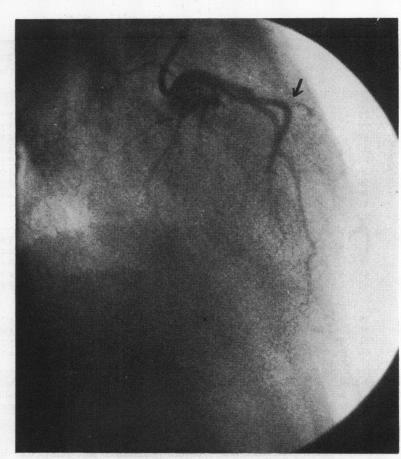

Selective coronary angiography in primary myocardial disease.

Br Heart J. 1973 Feb;35(2):165-73. doi: 10.1136/hrt.35.2.165.